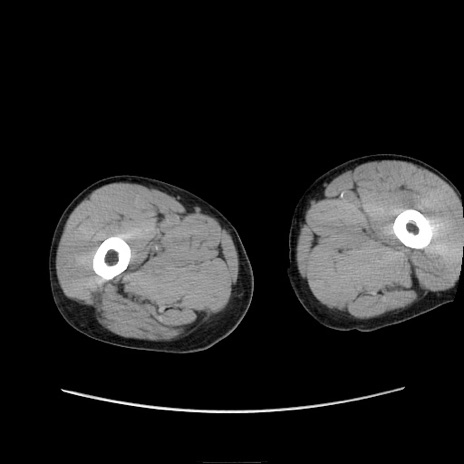

症例11(横断像)

【症例】 60歳代男性

【主訴】 下腹部痛

【現病歴】 本日夜中より下腹部痛の症状認め、受診。

【既往歴】 膀胱癌(膀胱全摘+尿管皮膚瘻術) 、胃癌術後

【身体所見】 BT 35.3℃、PR 58/min、BP 136/98mHg、腹部平坦、軟、腸蠕動音±、ストマ留置あり、左上腹部~正中部に圧痛あり、反跳痛なし。

【データ】WBC 5100、CRP0.01